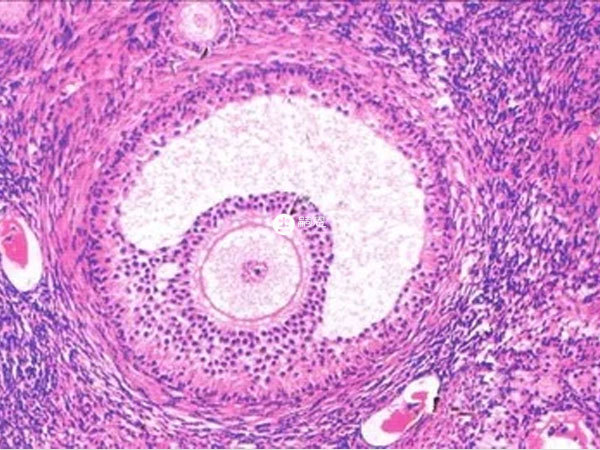

女,35歲,是因為卵巢早衰做的試管嬰兒,定的自然週期方案,因為卵巢功能低下的原因一直沒有有用的卵泡,我測了5個月的卵泡了,這個月第11天監測,左側有一個18x14,等我第15天監測15x12,之前15天卵泡都漲到20左右的,我這是之前成熟卵泡已經排出了嗎?卵泡排出後其他的卵泡還發育成優勢卵泡?一般情況下,在經過成熟卵泡排出後,卵巢內剩下的其他卵泡是不會繼續發育的,更不會發育成優勢卵泡了。在一個月經週期會有多個卵泡同時發育,但是每個卵泡的發育進度不一樣,大的、成熟的卵泡排出後,卵巢中會剩下較小的卵泡,而這些小的卵泡就會萎縮、閉鎖,不會再繼續生長了,建議在發現優勢卵泡後,可以及時的進行卵泡監測。

女性每個月經週期只會有一個優勢卵泡排出,在成熟卵泡排出後,其他卵泡是不會繼續發育的,這種情況一般是受激素的作用,下面可以詳細瞭解一下排卵後剩下的小卵泡會怎樣,具體如下: